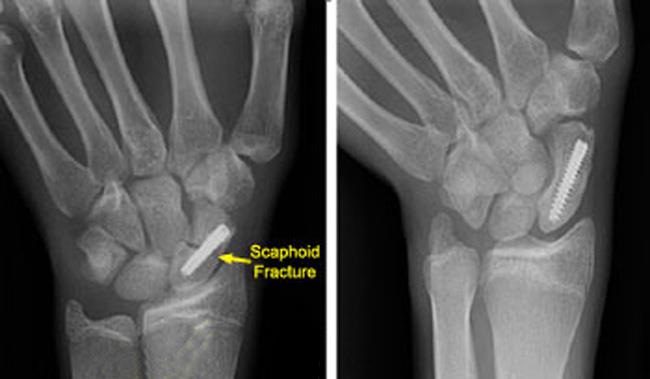

Upload Date: March 31, 2019 Full Size Image Dimensions: 650 × 379 Image Parent Post: Κατάγματα άνω άκρου

7.Εσωτερική οστεοσύνθεση κατάγματος σκαφοειδούς